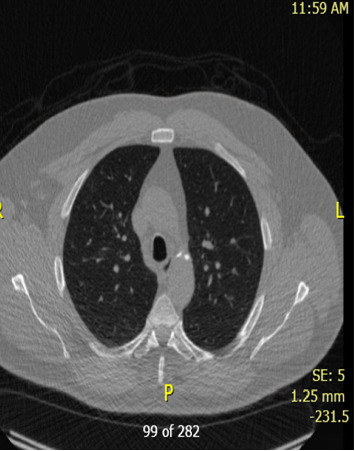

肾细胞癌(RCC)的幸存者,特别是肾切除术后,需要长期随访复发或全身并发症。当有肾细胞癌病史的患者出现肺结节时,我们必须考虑到感染性疾病,特别是那些环境暴露和与肾切除术后继发代谢变化相关的免疫改变的患者。我们报告了一位49岁男性患者,他在肾切除术后患有肾小细胞癌,有长期吸烟史,并有明显的煤尘暴露史,他发展为进行性肺结节。虽然最初怀疑为转移性肾细胞癌(mRCC),但连续影像学显示结节增大,PET扫描无代谢活动,需要进一步评估。鉴于持续的呼吸道症状,他接受了支气管镜检查并进行了微生物学分析,发现了烟熏曲霉,最终被诊断为慢性肺曲霉病。我们的患者成功地用伏立康唑治疗,并随着时间的推移显示出显著的临床改善。在本例中,我们观察了RCC幸存者肺结节的诊断困境,以及广泛鉴别以避免误诊的重要性。肾切除术后的免疫变化,可能伴有慢性肾脏疾病(CKD),或长期的肿瘤监测可能使患者处于机会性感染的危险之中。为了确保及时发现和治疗可能模拟肿瘤进展的感染,临床医生治疗RCC幸存者应将微生物学诊断纳入常规肺部评估。

Survivors of renal cell carcinoma (RCC), especially following nephrectomy, require long follow-up for recurrence or systemic complications. While those with a history of RCC develop pulmonary nodules often with concern for metastasis, we must consider infectious diseases, especially in patients with environmental exposures and immune alterations related to metabolic changes secondary to nephrectomy. We report a 49-year-old male with a history of RCC status postnephrectomy, history of long-term smoking, and history of significant coal dust exposure, who developed progressive pulmonary nodules. Although initially suspected to be metastatic RCC (mRCC), serial imaging demonstrated nodule enlargement without metabolic activity on PET scan, requiring further evaluation. Given the persistent respiratory symptoms, he underwent bronchoscopy with microbiologic analysis which identified Aspergillus fumigates and was ultimately diagnosed with chronic pulmonary aspergillosis. Our patient was successfully treated with voriconazole and over time demonstrated significant clinical improvement. In this case, we have made the observation of the diagnostic dilemma presented by the pulmonary nodules in RCC survivors and the importance of a broad differential to avoid misdiagnosis. Immune changes following nephrectomy, possible accompanying chronic kidney disease (CKD), or prolonged oncologic surveillance could place patients at risk for opportunistic infections. In order to ensure timely detection and treatment of infections that may mimic tumor progression, clinicians treating RCC survivors should integrate microbiologic diagnostics into routine pulmonary evaluations.